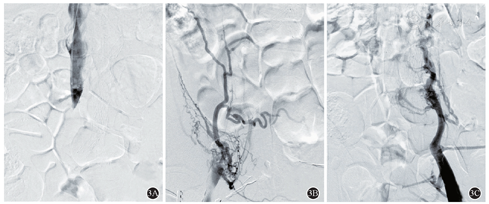

患者,男,51岁,因"反复双下肢水肿7月,右下肢肿胀加重3 d"为主诉入院。患者7月前无明显诱因出现双下肢肿胀,右侧较重,活动及久站后加重,晨起消失。无间歇性跛行及下肢疼痛,未诉腹部及背部疼痛病史。患者至医院行下肢深静脉彩超检查诊断为下肢静脉曲张并给予治疗后,患者症状反复。3 d前患者因"右下肢肿胀加重"至我院就诊。查体:右下肢肿胀,伴小腿胫前色素沉着,范围约6 cm×4 cm。彩超提示:右侧髂总静脉、髂外静脉、股总静脉上段血栓形成,腹主动脉瘤合并血栓形成。上腹部增强CT可见:腹主动脉下段局部管壁见小破口出血,周围组织包裹,血肿形成(图1A),下腔静脉、右侧髂总静脉、髂外静脉及股静脉上段可见充盈缺损影(图1B)。冠状位重建图像(图1C)显示腹主动脉的假性动脉瘤压迫下腔静脉,导致下腔静脉狭窄(图2A)。诊断明确后,行腹主动脉瘤腔内隔绝术(图2),术后3 d拟定行"下腔静脉造影并下肢静脉血栓清除术",术中造影可见下腔静脉下段闭塞,大量侧支循环形成(图3),开通困难。遂术后予以利伐沙班20 mg QD抗凝治疗。

本例患者由于下腔静脉压迫时间较长,血栓机化造成血栓后综合征,血管开通较为困难,给予术后抗凝治疗6个月,下肢的疼痛和水肿消失,随访期间无肺栓塞等不良事件发生。在一例个案报道中[2],由于患者就诊较早,给予下腔静脉滤器置入并置管溶栓术,下肢静脉血管开通情况较好。其余的相关报道对于DVT均采用阿派沙班抗凝治疗,无下肢DVT复发的证据。